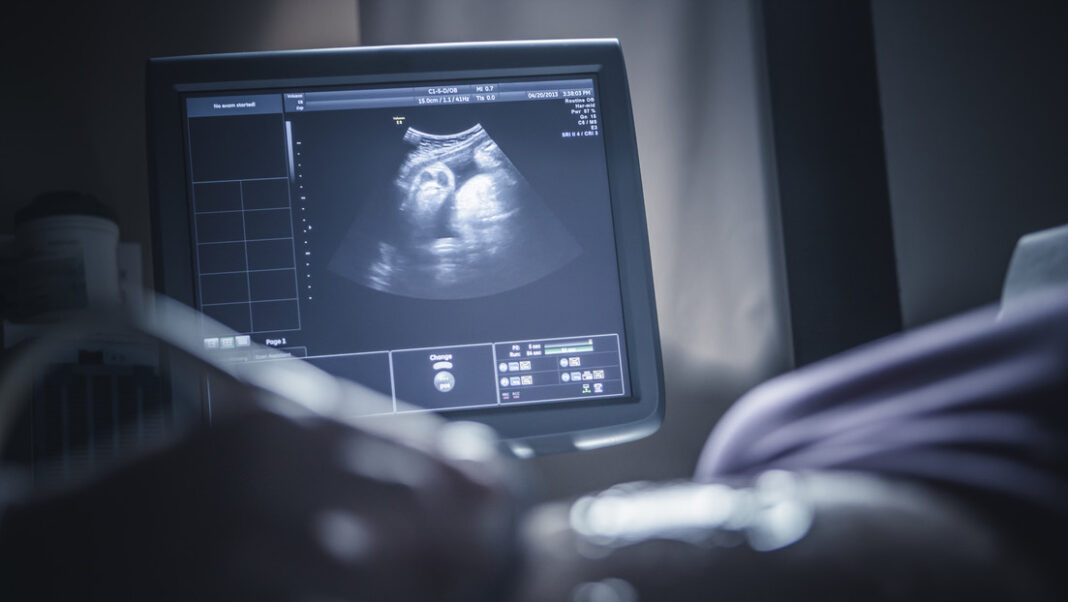

Según el informe del hospital donde se realizaron los estudios, la madre acudió inicialmente por molestias que consideraba normales del embarazo. Sin embargo, al efectuarle una ecografía detallada, los médicos identificaron la presencia de nueve fetos, algo que solo se ha registrado en contadas ocasiones en la historia de la medicina.